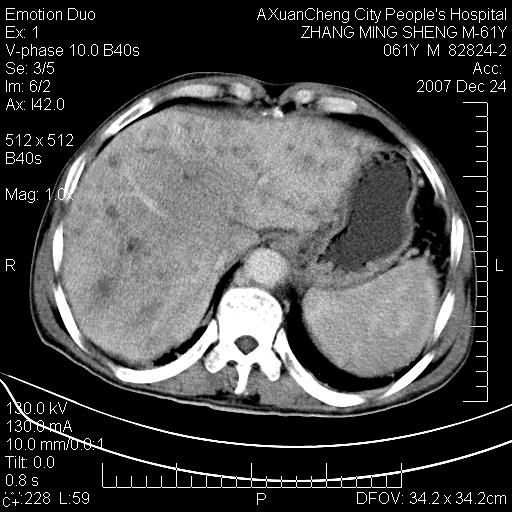

标题: CT11031:M61Y,胰腺占位

大家侃侃门静脉和胆管系统怎么回事,肝内转移?

胰腺癌肝转移

肝硬化,门脉高压,脾肿大;弥漫性肝癌,肝内、门脉、腹膜后淋巴结转移,肝内外胆管扩张,胰头区占位,建议mr检查

胰腺癌伴肝内转移;门脉、肠系膜上v癌栓形成。

考虑为:胰腺癌伴肝脏转移、腹膜后淋巴结转移,门静脉及肠系膜上静脉瘤栓形成。

胰体尾癌伴肝内转移,门静脉及肠系膜上静脉瘤栓形成.